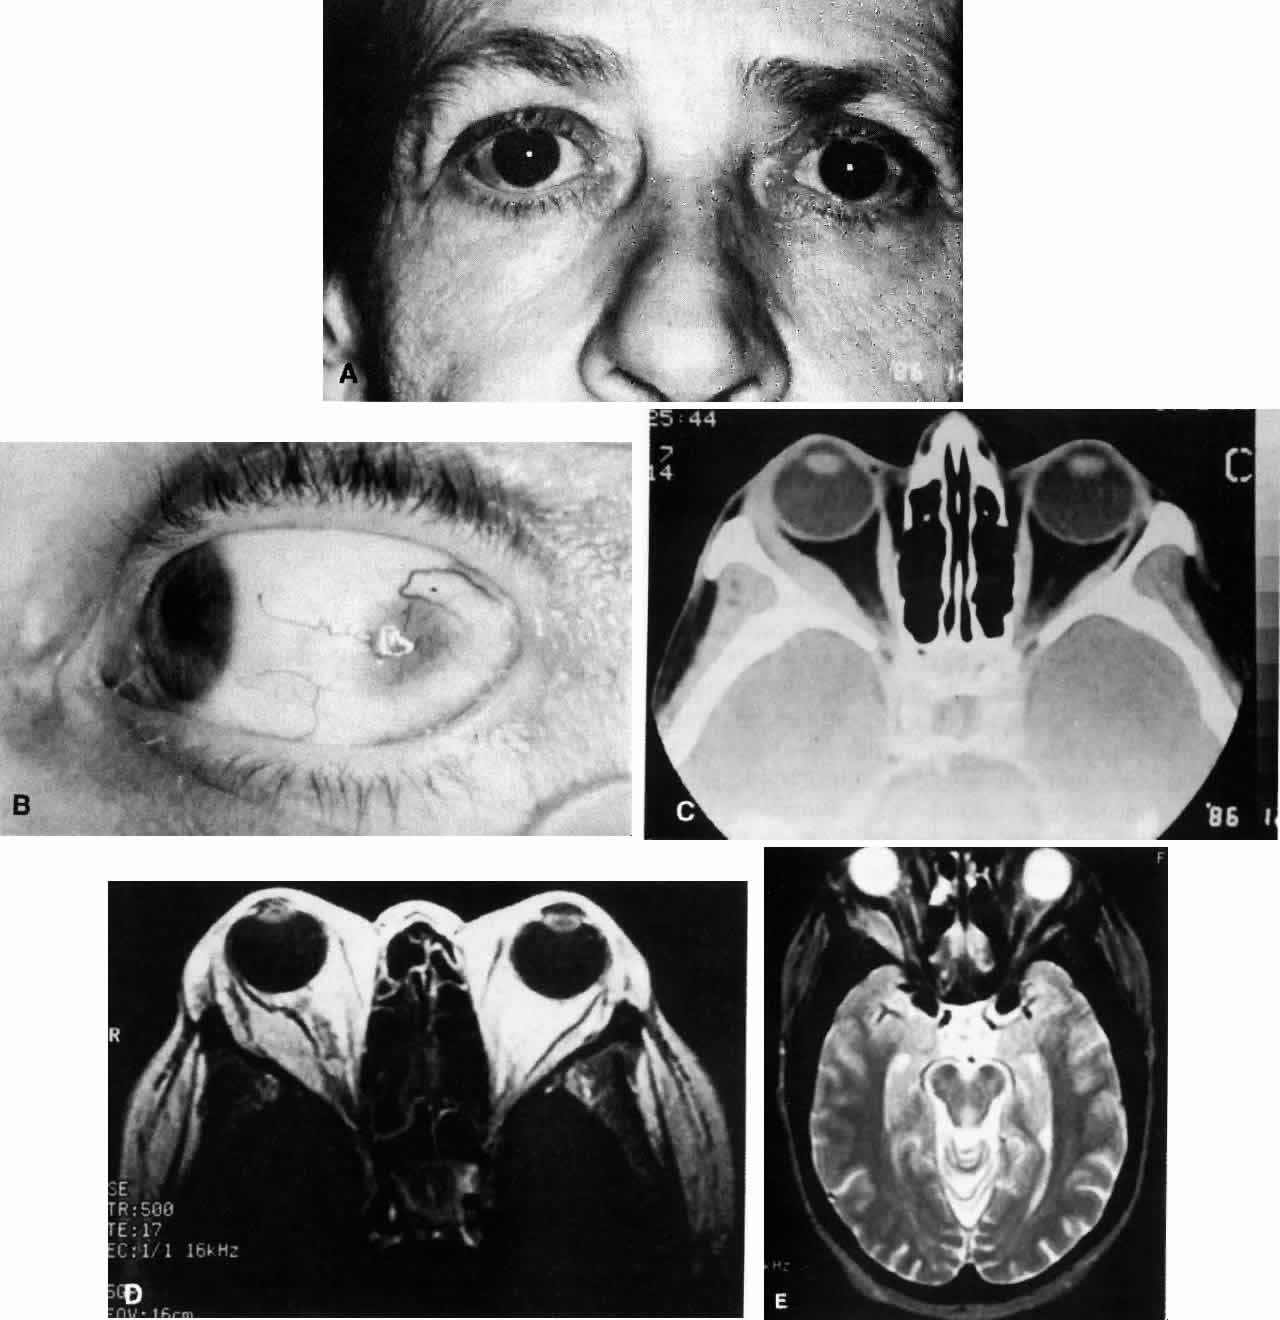

Fig. 2. A 54-year-old woman presented with acute orbital inflammation demonstrating significant proptosis and inflammatory signs involving the right orbit. In addition to severe pain, the patient had diplopia secondary to orbital edema and inflammation.

Fig. 3. A. A 62-year-old woman presented with diplopia and minimal right-sided proptosis. B. Enlarged lateral rectus muscle is visible subconjunctivally. C. Axial CT image confirms myositis involving the lateral rectus muscle. Note that the muscle as well as its tendon are involved in the inflammatory process in contrast to muscle involvement in thyroid-related orbital disease. D. T1-weighted MRI image demonstrating myositis involving the lateral rectus muscle. In this case the muscle belly is enlarged but the tendon appears relatively unaffected. E. T2 weighted MRI image of orbital myositis showing little difference in appearance of muscle between T1- and T2-weighted images.